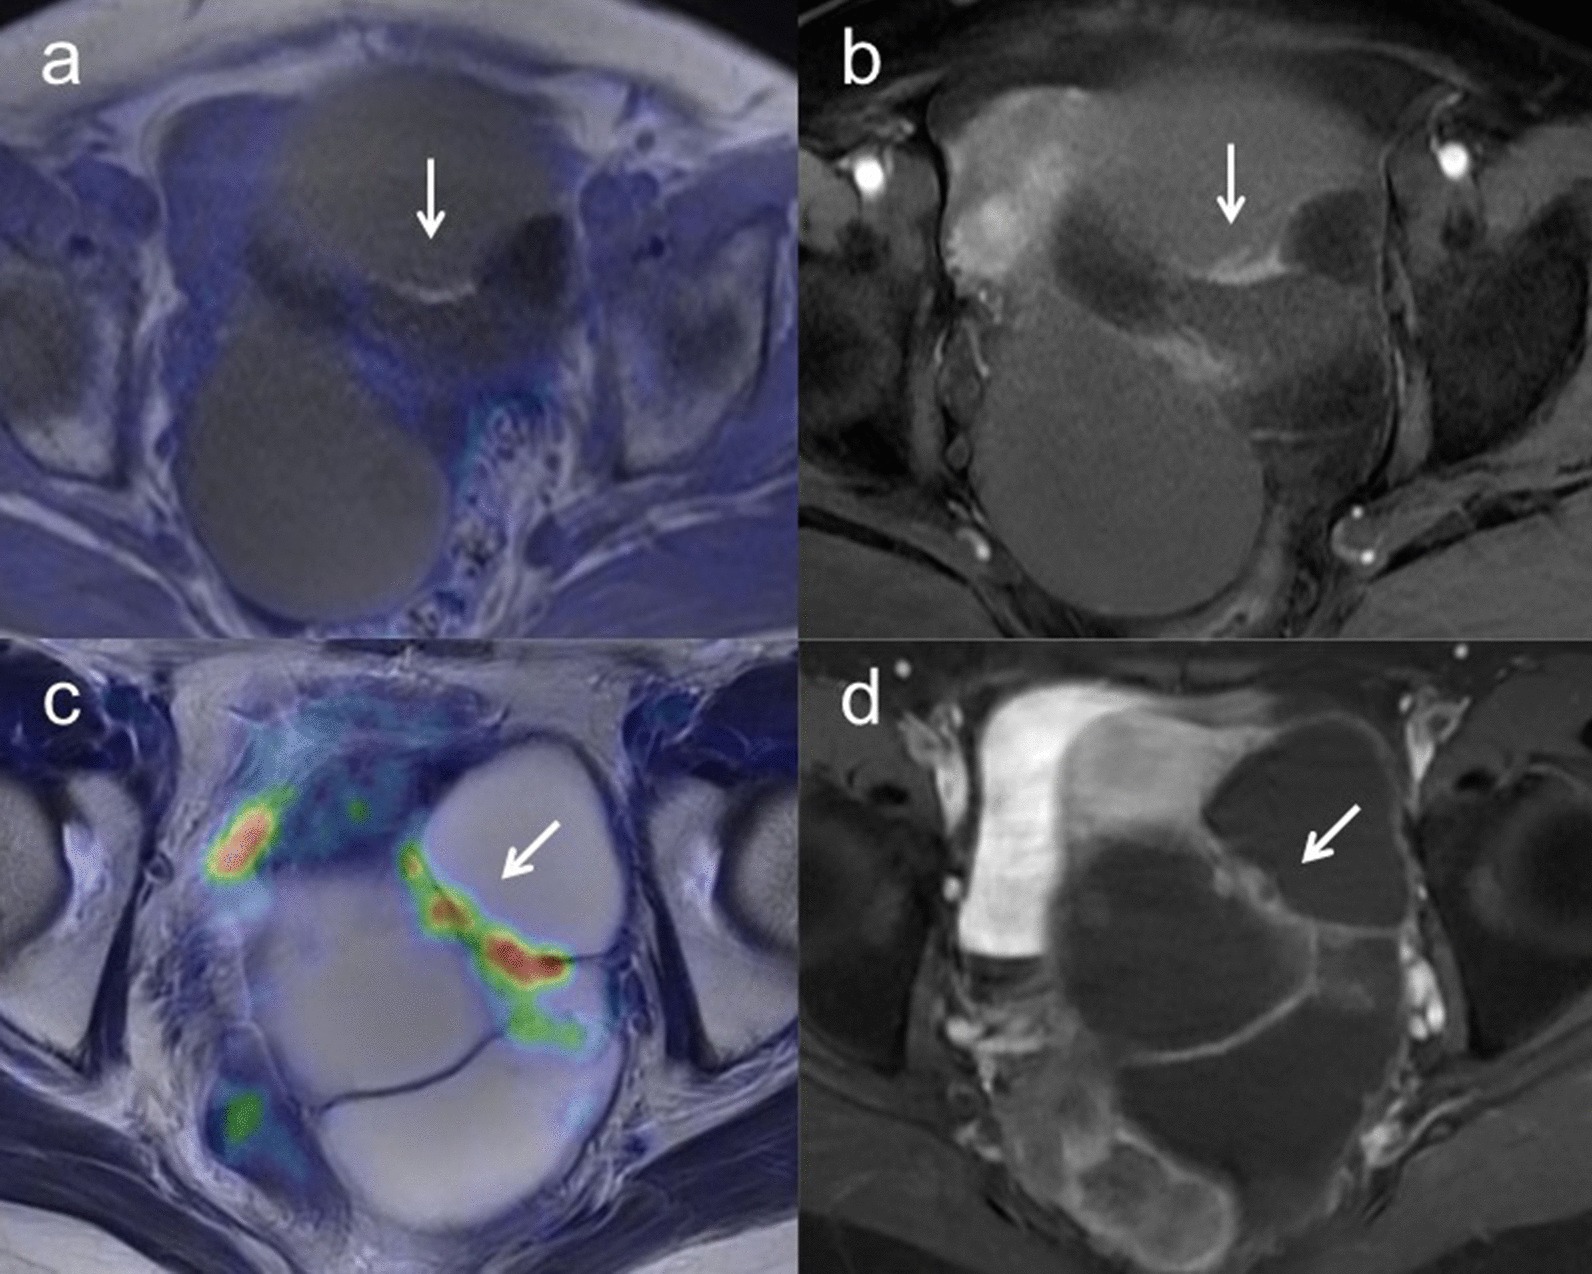

Sensitivity, specificity and accuracy for characterization were 97.4% [95% confidence interval (CI) 0.90–1.00], 86.2% (95% CI 0.77–0.89) and 92.5% (95% CI 0.84–0.95) for [18F]FDG PET/MRI and 97.4% (95% CI 0.89–1.00), 58.6% (95% CI 0.48–0.61) and 80.6% (95% CI 0.72–0.83) for ceMRI, respectively (p = 0.01) (Table 5). Figure 1 shows representative images for characterizations.

Fig. 1.

a A 57-year-old woman with left ovarian tumor. Axial T2-weighted PET/MR image shows wall thickening without FDG uptake (arrow) in the polycystic left ovarian tumor. b Axial T1-weighted contrast-enhanced MR image shows wall thickening with good enhancement (arrow), suggesting the possibility of malignancy. However, histopathologic examination confirmed mucinous cystadenoma without malignancy. c A 53-year-old woman with left ovarian tumor. Axial T2-weighted PET/MR image shows wall thickening with FDG uptake (arrow) in the polycystic left ovarian tumor. d Axial T1-weighted contrast-enhanced MR image shows wall thickening with good enhancement (arrow). These findings strongly suggest potential malignancy and histopathologic examination confirmed seromucinous borderline tumor